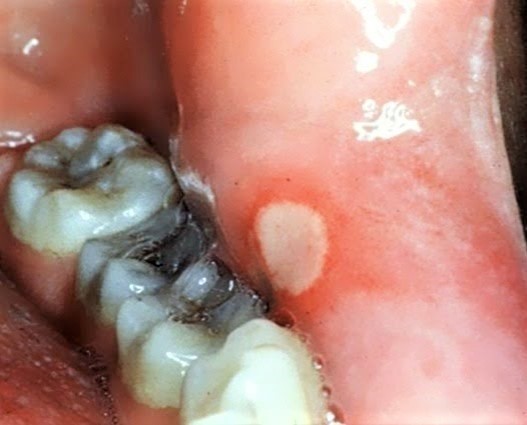

治りにくい白い口内炎!治療方法や口内炎ができやすい場所・種類別の原因を解説歯のアンテナ。

好きです: 471